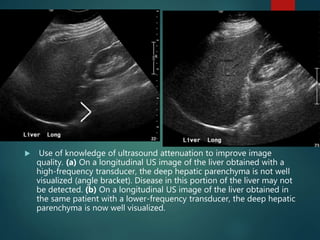

 Use of knowledge of ultrasound attenuation to improve image

quality. (a) On a longitudinal US image of the liver obtained with a

high-frequency transducer, the deep hepatic parenchyma is not well

visualized (angle bracket). Disease in this portion of the liver may not

be detected. (b) On a longitudinal US image of the liver obtained in

the same patient with a lower-frequency transducer, the deep hepatic

parenchyma is now well visualized.